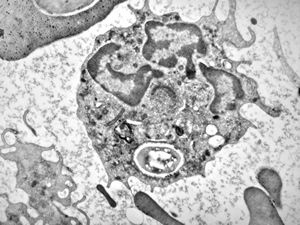

F,16y. | bone marrow -malignant histiocytosis

F,16y. | bone marrow - malignant histiocytosis